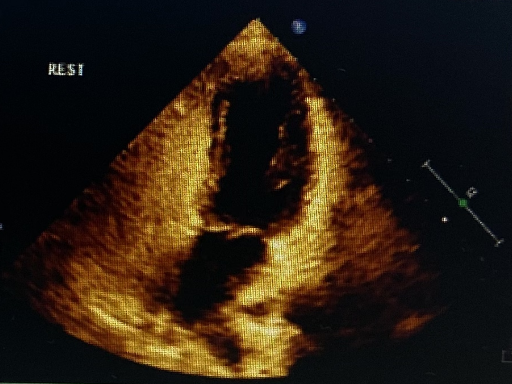

右心声学造影:静息状态下连续监测3个心动周期内,左心腔未见微泡通过,房水平右向左分流0级;继续观察超过6个心动周期亦无持续分流。然而在Valsalva释放时,左心腔内可见>30微泡/帧,判定为3级大量“一过性”房水平右向左分流,提示卵圆孔未闭可能性大。

静息状态下